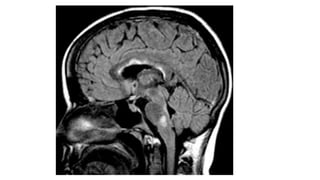

• Sagittal and coronal MRI images of Chiari type I malformation.

• descent of cerebellar tonsils (T) below the level of foramen magnum (white line) down to the level of C1 posterior arch (asterisk).

• Sagittal andcoronal MRI images of Chiari type I malformation. • descent of cerebellar tonsils (T) below the level of foramen magnum (white line) down to the level of C1 posterior arch (asterisk).

• #38 MRI is the procedure of choice for identifying Chiari malformations; midline sagittal sections clearly show the level of the cerebellar tonsils.